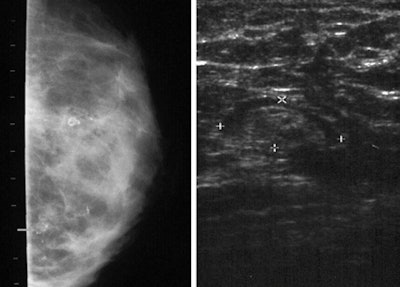

| Left: Clustered microcalcifications in the inferolateral area of the right breast cannot be distinguished from malignant calcifications. Right: Sonogram of the right axilla of the same patient shows a 1.0 x 0.8-cm lymph node. Images courtesy of Dr. Cong-Feng Wang. Reprinted with permission of the ASPS. |

Ten clustered microcalcifications had been identified in eight patients, five of which were palpable. Half of the clustered microcalcifications were located in the middle area of the breast.

Because the images of the microcalcifications were indistinguishable from malignant ones, biopsies were performed on each patient. None were cancers. Fat necroses were pathologically confirmed for all.